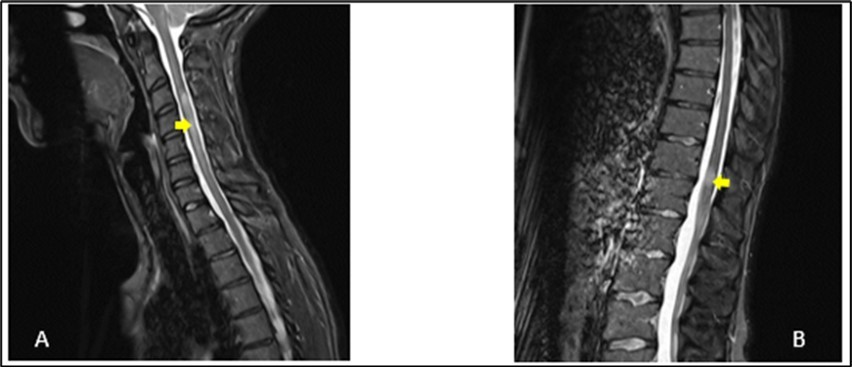

A 27-year-old girl presented at the emergency department, at a hospital in the Paris region on March 9, 2020 with complaints of left interscapular pain, paresthesias and weakness in the ipsilateral upper limb. These symptoms followed paresthesias on the fingertips of her right hand the day before her admission. She did not report fever, sphincter disorder or gait disturbance. No eye symptoms reported. In her medical history, she was treated two weeks earlier for pneumonia with COVID-19. There was no another previous infectious episode apart from the COVID-19. She had no history of diabetes, hypertension, cerebrovascular disease or migraine. She had not history of multiple sclerosis or Neuromyelitis Optica Spectrum Disorder (NMOSD). There was no history of smoking, contraception drugs intake or any prolonged drug intake. On the first examination in the neurology department where she was transferred on the same day of her admission, she had good general condition and was apyretic. She had a pulse rate of 74/min and the blood pressure was at 130/80 mmHg. The neurological evaluation showed on the left side, a muscular weakness grade 4 in the proximal part and grade 3 in the distal part of upper limb, and in the lower limb, the weakness graded at 3 in the distal part, using the Medical Research Council Scale (MRC) for muscle strength. There was no weakness on the right side. Deep tendon reflexes in both left and right were normal. Babinski sign was found on the left side. She presented tactil and algic hypoesthesia in the lower left limb ascending until the C4 level in the left side. There was no perineal sensitive trouble. The remain neurological exam including, higher functions, cranial nerves, was with no particularity. Otherwise, cardiovascular and respiratory systems examination were within normal limits. Blood laboratory tests were within the normal ranges, including complete blood count (CBC), C-Reactive protein, renal and liver functions and blood serum ionogram. Human Immunodeficiency Virus (HIV) tests including p24 antigen and antibodies to HIV were negative. Syphilis serology and Aquaporin 4 antibody were also negative. Encephalic Magnetic Resonance Imaging (MRI) demonstrated scattered hyperintense lesions on FLAIR imaging in deep hemispheric and juxtacortical white matter in supratentorial and in infratentorial floors (Figure 1). Medullary MRI showed T2 hyperintense lesions in left cervical hemi-marrow extending from C3 to C6, at T3, T4, T11 and T12 levels (Figure 2). These lesions were not enhanced after injection of gadolinium. The Cerebrospinal fluid (CSF) appeared to be colorless and clear with no cell detected microscopically; cerebrospinal protein level, 0.4 mg/L, glucose (Glu) level, 3.2 mmol/L; and instant blood glucose level, 5.2 mmol/L. CSF bacterial culture demonstrated no growth after 3 days, and herpes simplex virus 1 and 2, varicella-zoster virus test was negative. Reverse transcription-polymerase chain reaction (RT-PCR) assay test for COVID-19 was negative in the CSF. The final diagnosis was an ADEM secondary to novel coronavirus (nCov) infection. She was given methylprednisolone (1000 mg IV per day for 5 days) followed by Intravenous Immunoglobulin (IVIG) therapy at 0.4 g/kg daily for 5 days. Together with chemotherapy, she received physiotherapy coupled with occupational therapy. The outcome was good with improvement of weakness and paresthesias. There was residual tingling on the fingertips of the left hand. The patient was discharge on day 13.

Figure 2.Sagittal T2-weighted spine MRI showing at cervical level (A), a spontaneous hyperintense lesion of 5 cm from C3 to C6 and at thoracic level (B), a spontaneous hyperintense lesion of 1.5 cm from T11-T12